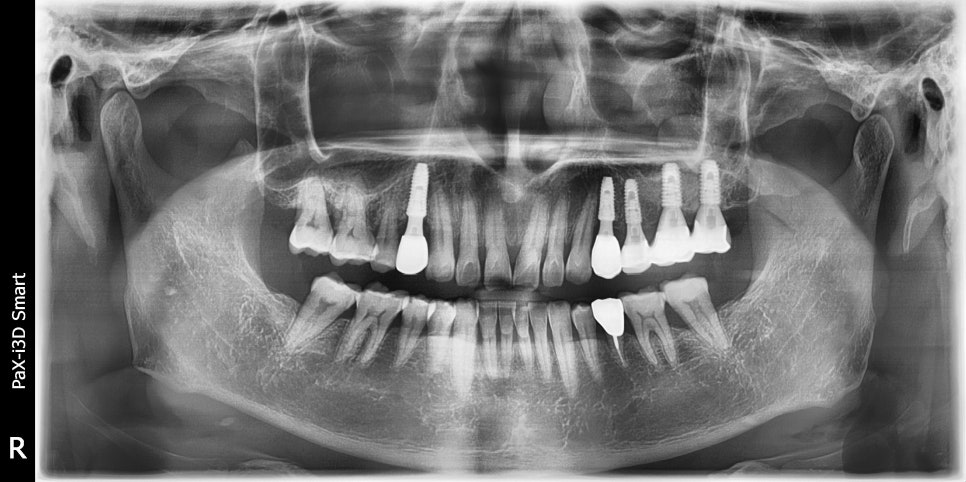

촬영일:2025.02.17(임플란트 3개 식립)

/ 2025.06.30 / 2025.07.11